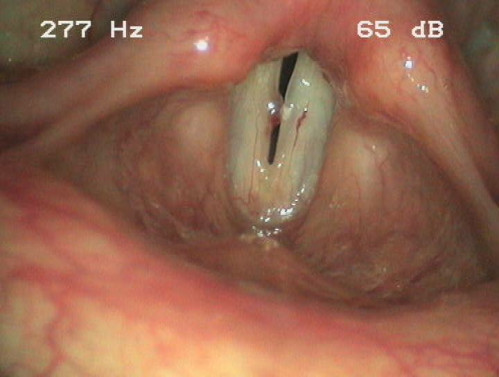

Eine 36-jährige klassische Sängerin klagt über Unsicherheiten beim Singen und über eine Rauhigkeit ihrer Stimme. Einen genauen Zeitpunkt des Beschwerdebeginns kann Sie nicht nennen. Die Problematik besteht jedoch seit mindestens einem halben Jahr.

Die Patientin fürchtet, dass die Ausübung ihres Berufes gefährdet ist.